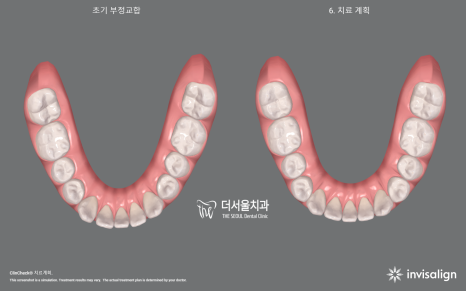

【 인비절라인 교정 진단 】

2급 부정교합 그리고

앞니 벌어짐을 인비절라인으로

개선을 돕기로 했습니다.

【 결과 】

앞니 벌어짐 은

반년이 채 걸리지 않아서 닫혀버렸습니다.

약 1년 반이 흐르고

2급 부정교합 및 하악 전치부 총생이

말끔히 없어졌네요.